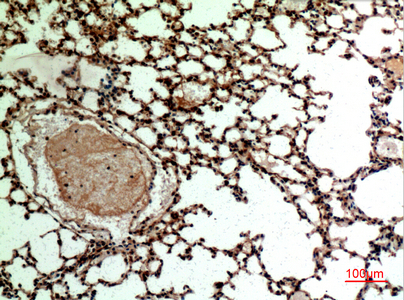

Immunohistochemistry analysis of paraffin-embedded mouse lung using CD62L antibody.High-pressure and temperature Sodium Citrate pH 6.0 was used for antigen retrieval. |